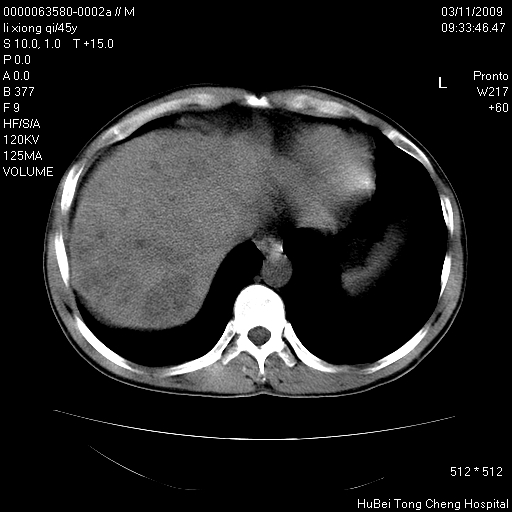

患者 男,45岁。胸痛,咳嗽伴痰中带血1月余。

临床诊断:肺结核?

胸部ct轴位平扫(层厚10mm,螺距1.5,重建间隔10mm),图像如下:

考虑肝癌肺转移